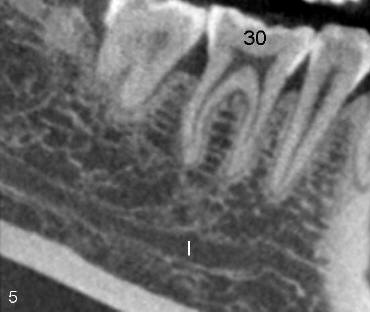

Post-operatively, the patient reports paresthesia of the lower left lip and tightness of the lower left teeth. The extent of paresthesia is marked and recorded 4 days after RCT retreat. In spite of some paresthesia improvement, CBCT is taken 24 days after RCT retreat. It shows that there is a communication (black and white < in Fig.6) between PARL (red <) and the inferior alveolar nerve (I). There are no similar findings (communication or PARL) on the right side (Fig.5).

Cross sections through the furcae of #30 and 19 re-confirm that trabecular patterns are normal under the furca of #30 (< in Fig.7), whereas there is abnormal communication between PARL (above black < in Fig.8) and the inferior alveolar nerve (I).

It is most likely that leaking of sodium hypochlorite (1.25%) and Chloroform through the enlarged pre-existing apical foramina causes temporary chemical burning of the inferior alveolar nerve through the abnormal communication and also by gravity. Mechanical mechanism such as extruded GP (< in Fig.9) is less likely.

The nature of the abnormal communication is intriguing. It may be an abnormal branch of the inferior alveolar nerve. The reasoning is that the border of this communication (between black and white < in Fig.6,8) is as smooth as that of the inferior alveolar nerve. In contrast, the border of PARL is irregular and rough. The second possibility is that this abnormal communication is a pathological change similar to PARL. We may get an answer if we can follow up the case closely. If this RCT retreat proves to be successful, PA will be taken every 6 months. Once periapical lesion heals unambiguously in traditional X-ray, CBCT is retaken. If PARL disappears whereas the abnormal communication does not, the hypothesis of abnormal branch of the inferior alveolar nerve is established. This proves to be bad news for implantologist. He has less bone height (~ 6 mm in this case) to place an implant in the first molar area (Fig.6). The second possibility is that both PARL and the abnormal communication disappear together. To retreat overfilled cases, control of WL is paramount.